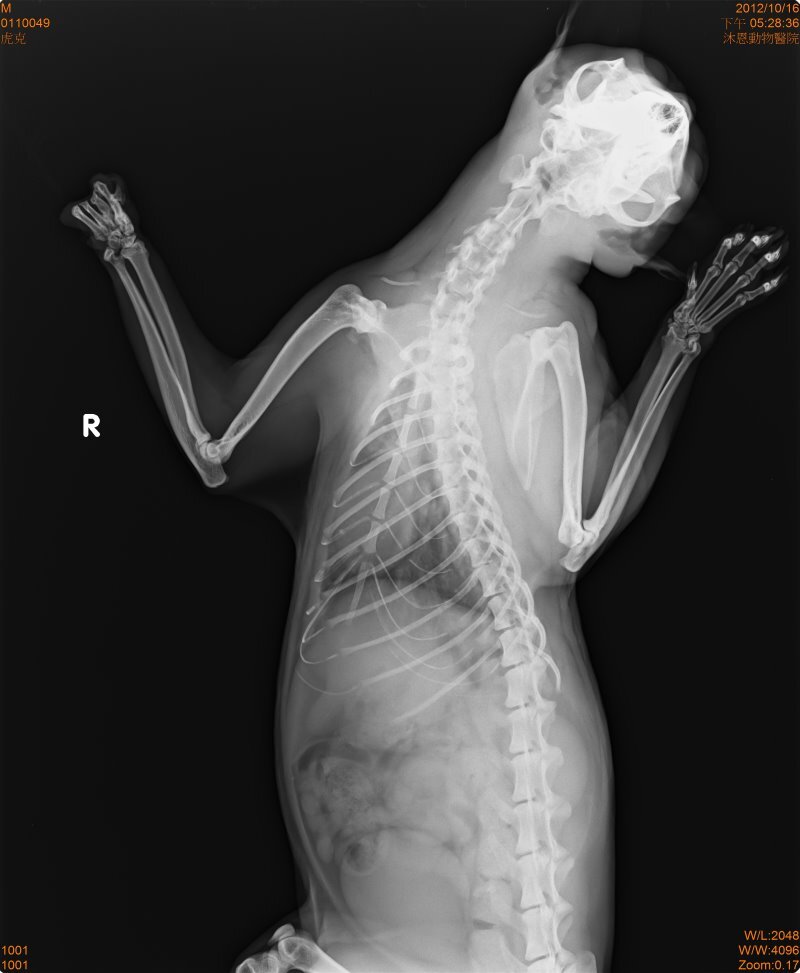

主題: 斷掌的虎斑公貓--虎克 申請者姓名: 蔡葦澄 花色: 申請日期: 2012-11-16 01:30:49 申請者部落格: 申請者臉書網址: 所在縣市/合作醫院: 台北市/其他院所醫助專案(醫院請先MAIL溝通) 治療費用: 12800元 需求人數: 28人 已結案 (2013-06-13 11:58:04) 報名人員: April Tsung(已付款)、Sean Chun-hsiang Yo(已付款)、阿蓋 (已付款)、chiawei(已付款)、柳佳豪(已付款)、Ting-Hsuan Tseng(已付款)、Yiling Tsai(已付款)、leehiromi(已付款)、謝沛豈(已付款)、黃小紅(已付款)、Joyce Chung(已付款)、Monica Hu(已付款)、clement(已付款)、shuwen(已付款)、Corrie Tan(已付款)、Carol Kuo(已付款)、Chiao-Hsin Yu(已付款)、斑斑姊(已付款)、柯元傑(已付款)、春卷(已付款)、Patrick Liu(已付款)、Ching Yi Hsieh(已付款)、Sean Chun-hsiang Yo(已付款)、Angel Li(已付款)、喵媽(已付款)、喵媽(已付款)、Summer(已付款)、chapi(已付款)、 候補人員: 動物病情說明: 網友求援在大安區SOGO附近的安東街,有美短紋路的貓咪左眼受傷需要醫療。前去該地區騎車繞了好幾圈並沒有看到眼睛受傷的貓,從超商旁騎過看到一個影子閃進防火巷(有鐵門)放了點罐頭,貓有跑出來吃,設了誘捕籠躲在旁邊,看見貓一拐一拐地走進去,門關起來後也沒有很激動,稍微看一下發現貓貓沒有手掌,X光檢查後將傷口做縫合,因為斷處還保有肉墊,可供行走用,不需截肢,等傷口復原進行結紮,目前恢復狀況良好以R回原處,醫療費用還請各位幫忙。